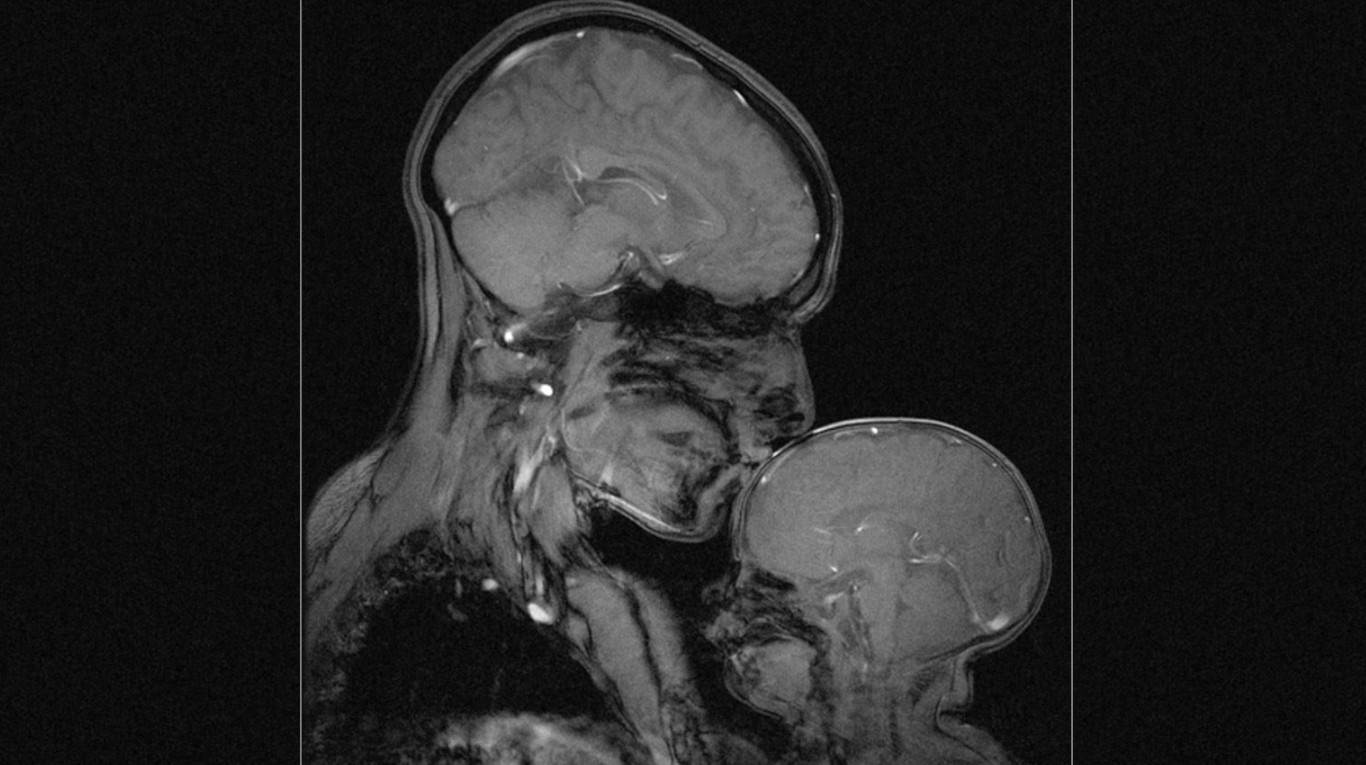

Kaže kako je istraživanje bebina mozga neophodno za razumijevanje ljudskog mozga i njegovih funkcija, eventualnih bolesti i oštećenja.

Iako su bebe nezahvalne za istraživanje jer su nepredvidive, Rebecca smatra kako se u bebinim mozgovima kriju odgovori na mnoga važna pitanja iz područja neuroznanosti. Ovakva nam istraživanja pomažu da osvijestimo moždanu osjetljivost, ali i otpornost, a ovaj čudesan portret podsjetnik je na to koliko toga zaista dijelimo s drugima, a koliko smo jedinstveni i svoji.